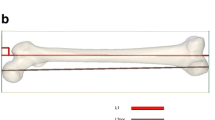

3D images of bilateral lower limb long bones, including the femur, tibia, fibula, and first metatarsus, were virtually reconstructed on the automated CT image analyzing system Volume Analyzer SYNAPSE VINCENT version 3 (FUJIFILM Medical Co., Ltd., Tokyo), identifying each bone shape based on the manufacturer’s graph-cut algorithm, which automatically estimates the CT value distribution and optimal boundary for region segmentation of the bones without users’ intervention [23, 34, 35]. The first metatarsus was chosen because it is a well-preserved foot bone in decomposed bodies and easy to identify when recovered separately [36]. Measured parameters were bone mass volume (cm3), maximum (max.) length (mm) (vertical distance between proximal and distal endpoints) (Supplementary Fig. S1), and the mean CT attenuation (HU) value and total CT attenuation (HU) value (mean HU × bone volume). The mean CT attenuation (HU) value was automatically provided for the whole extracted bone. Manual 3D measurement of the bone length was performed by three independent observers, and intraobserver and interobserver precisions were examined by applying three widely used precision estimates: the technical error of measurement (TEM), the relative technical error of measurement (rTEM), and the coefficient of reliability (R) [16]. Virtual measurements of the maximum bone length were compared with the manual measurements using skeletonized dry bone samples of the femur, tibia, and fibula (n = 7 for each) to examine the reliability. These measurements were repeated two times for each bone.

The correlations between max. bone lengths and the stature were positive and significant in all cases (r = 0.42–0.85, SEE = 4.81–8.57 cm, p < 0.0001), and also in males (r = 0.33–0.74, SEE = 4.72–6.49 cm, p < 0.0001) and females (r = 0.55–0.85, SEE = 4.17–6.64 cm, p < 0.0001); however, lower correlations with greater SEE were detected for the first metatarsus (r = 0.33–0.68, SEE = 5.79–8.57 cm, p < 0.0001) than for the other bones (r = 0.71–0.85, SEE = 4.17–5.35 cm, p < 0.0001) (Table 3 and Supplementary Fig. S2). Bone mass volumes showed correlations with the statures in all cases, and in males and females (r = 0.58–0.83, SEE = 4.93–6.15 cm, p < 0.0001); the correlation of the first metatarsus (r = 0.58–0 77, SEE = 5.70–6.15 cm, p < 0.0001) was higher than that for the length (Table 3 and Supplementary Fig. S2). Mean HU value showed an age-dependent decrease in all cases, and in males and females (r = −0.30 to −0.83, p = 0.0002 for male right femur and p < 0.0001 for the others), showing significant difference between females of <60 and >60 years of age (p < 0.0001, Fig. 1); however, total CT attenuation value (HU) correlated with the stature in all cases, and in males and females (r = 0.62–0.82, SEE = 5.02–6.04 cm, p < 0.0001) (Table 3 and Supplementary Fig. S2). There was a substantial right-left difference in max. length of the first metatarsus (r = 0.69, p < 0.0001); however, such bilateral asymmetry was not significant for the first metatarsal volume and each parameter of the other bones (r = 0.92–0.99, p < 0.0001). As above, correlations with the stature were similar for the lengths and mass volumes of the femur, tibia, and fibula but were higher for the mass volume of the first metatarsus without bilateral asymmetry, showing regression equations for stature estimation using bilateral data: 30.037 + (0.309 * max. femur length); 40.638 + (0.361 * max. tibia length); 36.392 + (0.368 * max. fibula length); and 123.607 + (2.151 * first metatarsal volume). When the sampling error was examined by random resampling and recalculation, reducing sample numbers to 100 and 50, the correlations between the stature and individual parameters (r values) did not show significant difference (<0.05).

In the estimation of stature from separate single bones, the most common method is linear regression [43]. Since individual height is influenced by ethnicity and changes over time, it is recommended to use the updated regression formulae derived from the relevant population [44]. In the present study, the measurements of bilateral bones showed no significant difference for femur, tibia, and fibula, and the maximum lengths highly correlated with the stature both in males and female, as previously reported [45, 46]. However, the max. length of the first metatarsus showed lower correlations with the stature, involving substantial bilateral asymmetry. A previous study suggested a higher correlation with stature for the length of second metatarsus [47]; in the present study, however, for the first metatarsus, which is more easily identifiable when separately recovered, mass volume of the first metatarsus was a more adequate indicator for stature estimation than its max. length, suggesting the efficacy of CT volumetry. In stature estimation using individual bone parameters, the accuracies as estimated from 95 % confidence were higher (around 70 %) for mixed-sex groups than for male and female groups (around 60 %), as previously reported for foot measurements [1, 48], indicating that some skeletal variants are included both in males and females. This suggests that the accuracy of stature estimation is not improved by preliminary sex discrimination. Small intraobserver and interobserver deviations (<1.5 and <2 %, respectively) indicated the reliability of the virtual measurement, and a difference of <2 mm between the virtual and manual measurements using skeletonized dry bones is considered an acceptable range of error in forensic anthropology [49]. In postmortem measurement, a difference from antemortem statures (around 2.5-cm increase after death) should be taken in consideration [50]; however, comparisons with previous procedures for Japanese demonstrated the higher-level accuracy of the present procedure.